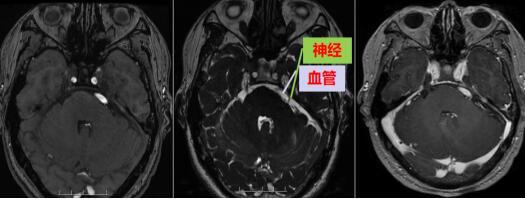

接诊的是神经外十科主治医师李兴可,充分了解吴先生的病情后,给予完善颅脑磁共振检查,明确诊断为“左侧三叉神经痛”。

“病因是因为颅内血管压迫了三叉神经颅内段导致的疼痛,治疗上可以采用微血管减压术,即使用一个小垫片,把血管和神经垫开就可以从病因上解决这个病症。”与吴先生详细交代病情并取得同意后,在全麻下行“左侧三叉神经微血管减压术”,术后吴先生诉疼痛立即消失。检查面部感觉无减退,听力无下降,无面瘫。